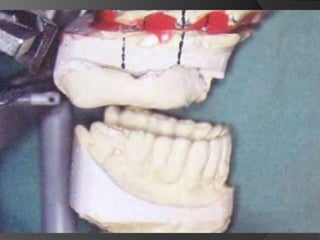

Diagnóstico y Planificación MultidisciplinariaEl examen clínico y la historia clínica nos darán información sobre los factores locales y sistémicos que pueden tener gran influencia en la obtención de un pronóstico para el tratamiento propuesto

Diagnóstico y Planificación MultidisciplinariaHistoria ClínicaAnamnesisFotografía clínica Montaje modelos de estudioEncerados DiagnósticosEvaluación Radiográfica Radiografías PeriapicalesRadiografía PanorámicaEvaluación DentalEvaluación PeriodontalEvaluación EndodónticaEvaluación OclusalEvaluación Articular?